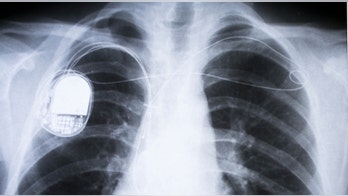

Medical Tech April 13, 2019 Hackers can access pacemakers, but don't panic just yet Bad guys can hack your heart.